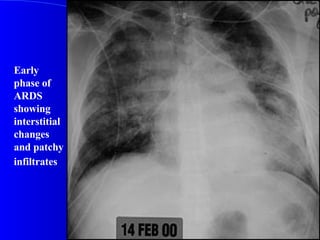

Early phase of ARDS showing interstitial changes and patchy infiltrates

Early phase ofARDS showing interstitial changes and patchy infiltrates